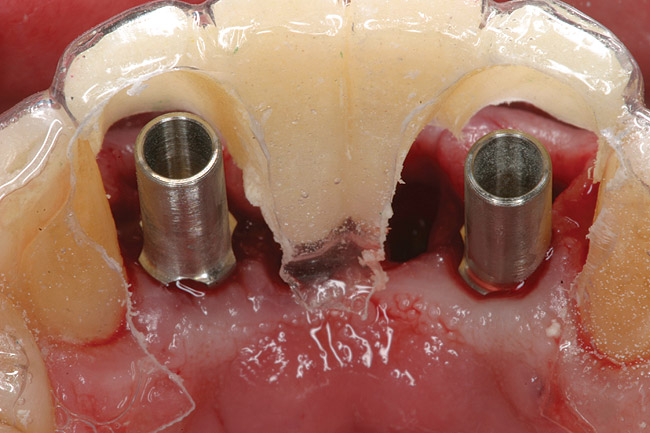

Preoperatively, 1 g of amoxicillin was administered. Using local anesthesia (lidocaine 1:100,000 epinephrine), extractions of teeth Nos. 23 to 26 were performed without raising a flap and with gentle luxation to preserve the remaining facial osseous plate. The sockets were curetted prior to implant placement. A vacuum-formed surgical guide, fabricated based on a diagnostic wax-up of the desired tooth positions for the subsequent fixed prosthesis, was used during implant placement. Osteotomies were performed at site Nos. 23 and 26 and positioned toward the lingual aspects of the sockets (Figure 3 and Figure 4). Two tapered implants (OsseoTite™ 313, BIOMET 3i™, www.biomet3i.com) measuring 3.25 mm x 13 mm were placed. Conical prosthetic abutments (3-mm height) were used to facilitate joining the two implants in a screw-retained FPD (Figure 5). A laboratory-processed acrylic-resin provisional restoration was altered to allow connection to the temporary cylinders. The provisional was placed into the vacuum-formed surgical guide that was now used to maintain the provisional in the correct 3-dimensional position (Figure 6) while being attached to the temporary cylinders with acrylic resin intraorally. Once a sufficient amount of acrylic resin was placed to secure the cylinders to the provisional, it was removed from the mouth and its contours were completed at the laboratory bench (Figure 7). The two central incisor sockets were grafted with small-particle allograft material (Puros® Allograft, Zimmer Dental, www.zimmer.com) to maintain the gingival architecture beneath the two ovate pontics (Figure 8). The provisional restoration was inserted and the screws were tightened to 20 Ncm of torque.

Figure 3  Osteotomies were prepared lingually.

Figure 3

Figure 4  Implants were placed without flap elevation.

Figure 4

Figure 5  Tapered implants with conical transgingival abutments and temporary cylinders in place.

Figure 5